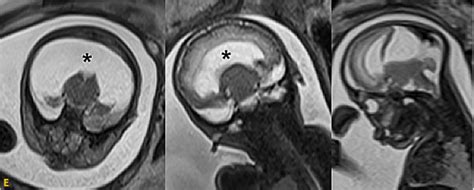

胎儿畸形是现在医学上很严重的一个问题,既是医生们想要攻破的一个难题,也是孕妈们最担心害怕的问题。因为导致胎儿畸形的原因有很多。据人民日报报道:据报道:全国不到30秒就有一名缺陷儿出生;将近一成的家庭承受过或正在承受生出缺陷患儿带来的不幸,在严重出生缺陷患儿中,约40%将成终生残疾,遗传因素25%环境因素10%,孕妇自身生理因素等其他因素65%。宝宝的健康出生是每个家庭的期望,而定期进行产前检直能够有效预防先天缺陷儿的出生,但是这些东西产检也很难查出来!

其实这几类畸形儿,在产检的时候藏得很深,很难检查出来。

1、先天性发育异常

胎儿如果是先天性发育异常就很难在检查时查出来,先天性疾病是一出生就有的病,很可能是因为母亲在怀孕期间接触到有害的环境,比如农药、有机溶剂、 重金属等化学品,或由于工作环境等原因过量暴露在各种射线下,或服用某些药物,或染上某些病菌,甚至一些不良的习惯爱好抽烟喝酒,都可能引起胎儿先天异常。